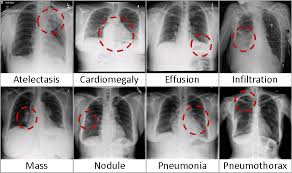

Chestx Ray8 Hospital Scale Chest X Ray Database And Benchmarks On Weakly Supervised Classification And Localization Of Common Thorax Diseases Arxiv Vanity